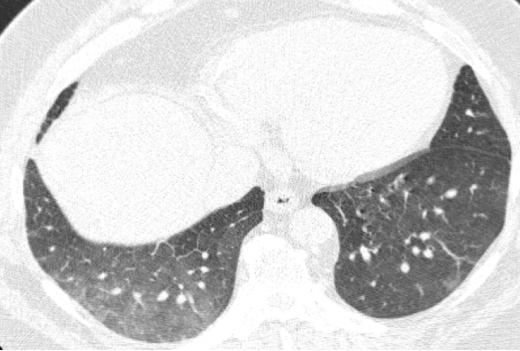

病例:男性,33岁,劳力性呼吸困难4年,加重3月,在治疗之前,我们看到的影像有些磨玻璃影、马赛克征,还有小叶中央型结节,并进行了外科肺活检。患者在从事铸造工作过程中间断接触异氰酸酯。停止工作暴露,并糖皮质激素经过治疗后,病情好转,但停用激素后又出现了肺部弥漫的磨玻璃影,肺功能也有所下降。

图:(从左至右)治疗前、脱离暴露+激素治疗10月、停激素18月